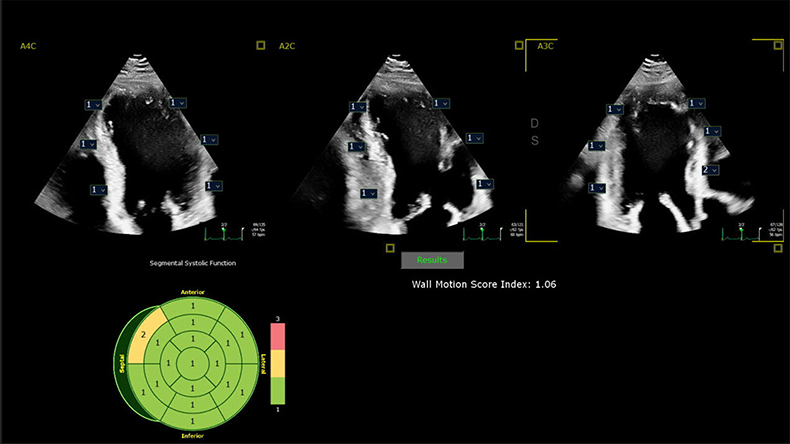

Dr. Lang heeft samen met andere artsen nieuwe inzichten gepresenteerd tijdens de jaarlijkse bijeenkomst van de American Society of Echocardiography (ASE2024) die van 14 t/m 16 juni plaatsvindt in Portland, VS. Hierin wordt uitgelegd hoe in samenwerking met Philips ontwikkelde AI-algoritmen op zeer nauwkeurige wijze regional wall motion abnormalities (RWMA) kunnen detecteren. RWMA's kunnen een indicator zijn van cardiovasculaire voorvallen en overlijden bij patiënten met hart- en vaatziekten, zoals een hartinfarct (myocardial infarction) en aangeboren hartaandoeningen. Geautomatiseerde, op machine learning gebaseerde beoordeling van RWMA’s heeft de potentie om cardiologen en echolaboranten verder te ondersteunen en efficiënter te werken verbeteren. "Een voordeel van AI ten opzichte van conventionele visuele analyse is dat deze binnen enkele seconden kunnen worden uitgevoerd, waardoor snelle en nauwkeurige informatie wordt verkregen; de analyse door deskundigen wordt verbeterd doordat zorgelijke RWMA's snel worden geïdentificeerd, waardoor de interpretatie eenvoudiger en efficiënter wordt," vertelt Lang.